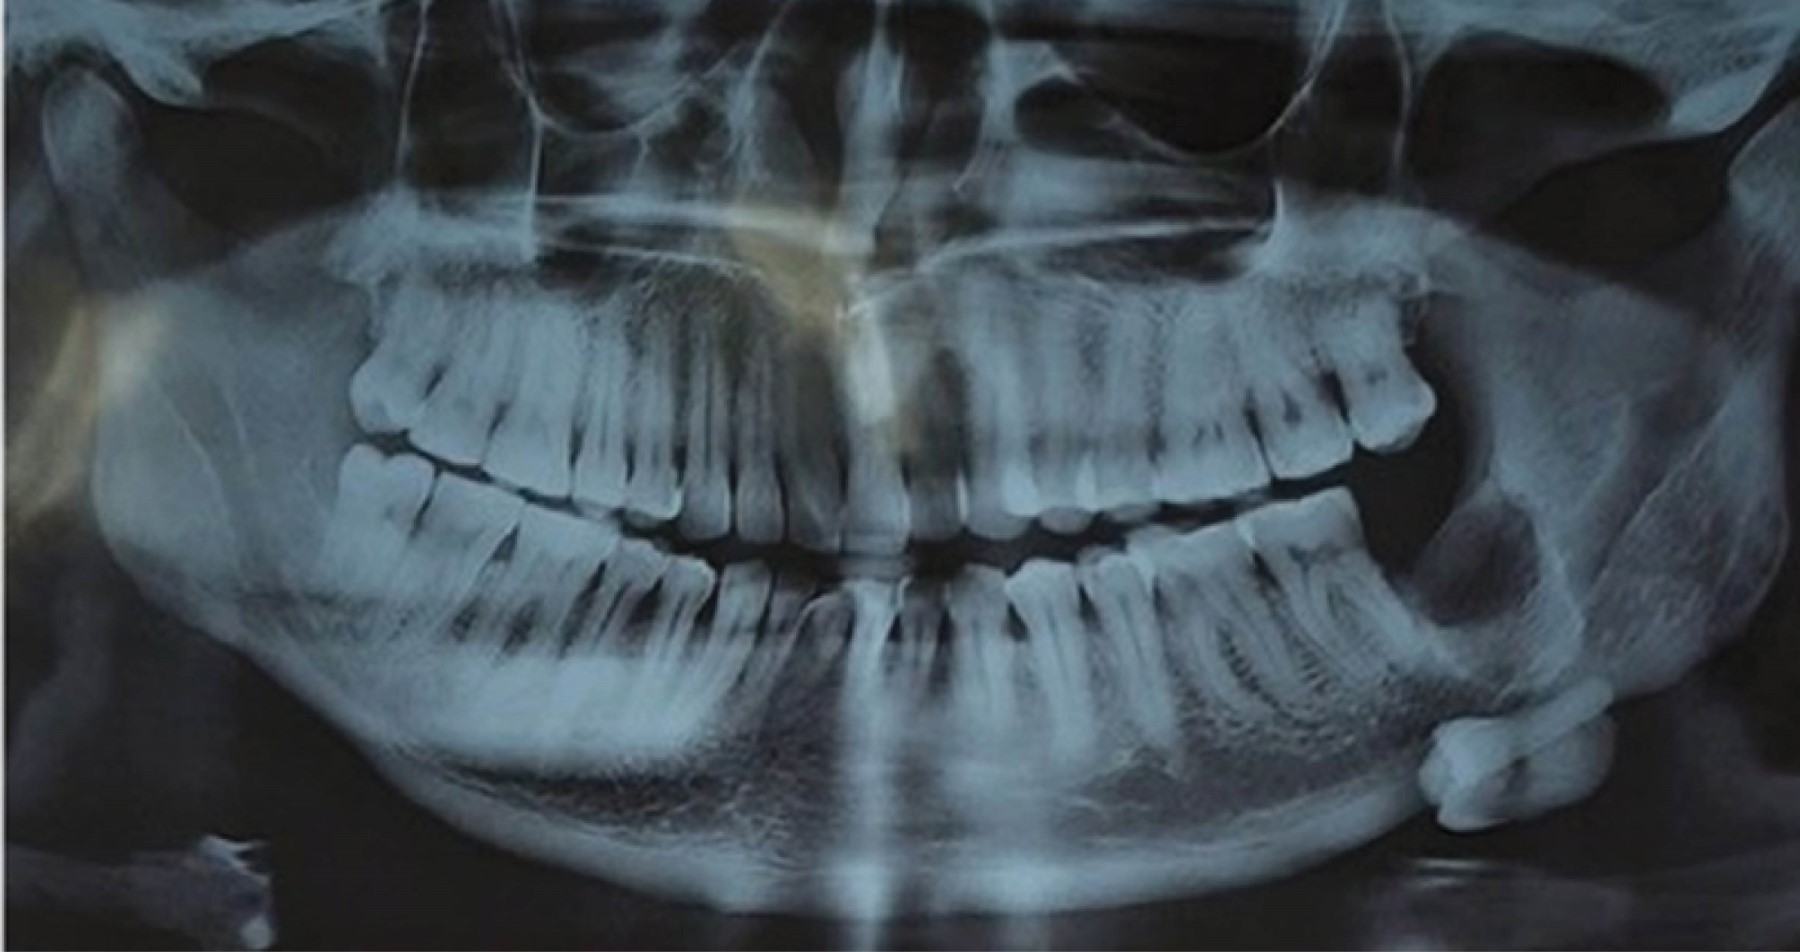

Tal como se refleja en el estudio realizado por Masui M y colaboradores denominado Displacement of lower third molar into floor of mouth: a single institutional experience,8 en el cual desarrollaron un análisis retrospectivo del manejo del tercer molar inferior desplazado hacia el piso de la boca, tomando en cuenta siete pacientes cuyo rango de edades iba de los 20-62 años, entre un periodo de tiempo que abarca del 2010-2020, el cual obtuvo como resultado: seis casos en donde el tercer molar fue desplazado hacia el espacio submandibular y un caso al espacio sublingual. Estas unidades dentarias o fragmentos dentarios, fueron retirados de piso de boca a través de un abordaje intraoral en seis casos, ya que únicamente un caso no se abordó; cuatro casos fueron abordados bajo anestesia general y dos casos bajo anestesia local, al igual que como expresan Tilaveridis I y asociados en el estudio denominado Displacement of maxillary third molar into the infratemporal fossa. A case report9 en donde se reportó el caso de un paciente masculino de 17 años de edad con desplazamiento de tercer molar superior izquierdo, luego de la evaluación de la tomografía computarizada se pudo evidenciar la presencia del tercer molar desplazado en la fosa infratemporal ipsilateral (Figura 1), su intervención fue bajo anestesia general, a través de un abordaje intraoral, en el cual la recuperación de la unidad fue de manera exitosa (Figura 2). De igual manera, Rivas y colegas en su estudio Tercer molar desplazado a fosa pterigomaxilar: reporte de caso5 presentan el caso de un paciente de sexo femenino de 16 años de edad, durante la cirugía de los terceros molares, la unidad 28 fue perdida de vista por parte del operador, indicaron radiografías panorámicas y tomografía de haz helicoidal, después de su evaluación se evidenció la ubicación de la unidad, el cual se encontró en la fosa pterigomaxilar (Figuras 3 y 4). Se realizó un abordaje intraoral bajo anestesia local, hasta alcanzar la unidad dentaria desplazada y recuperarla de manera exitosa.

Figura 3

Figura 4